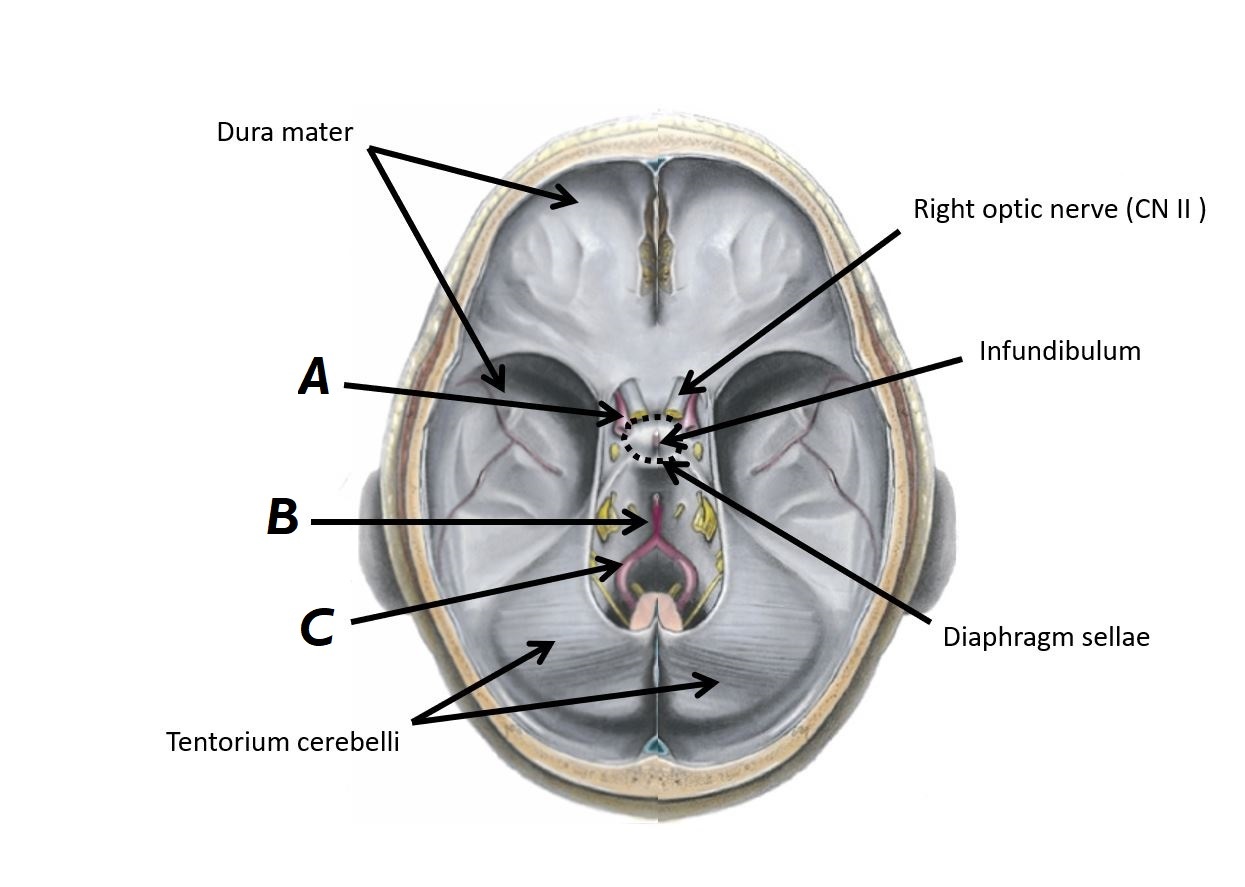

Name structure A and region B

A - Infundibulum

B - Diaphragm sellae

Name structures A, B and C

A - Left internal carotid artery

B - Basilar artery

C - Left vertebral artery